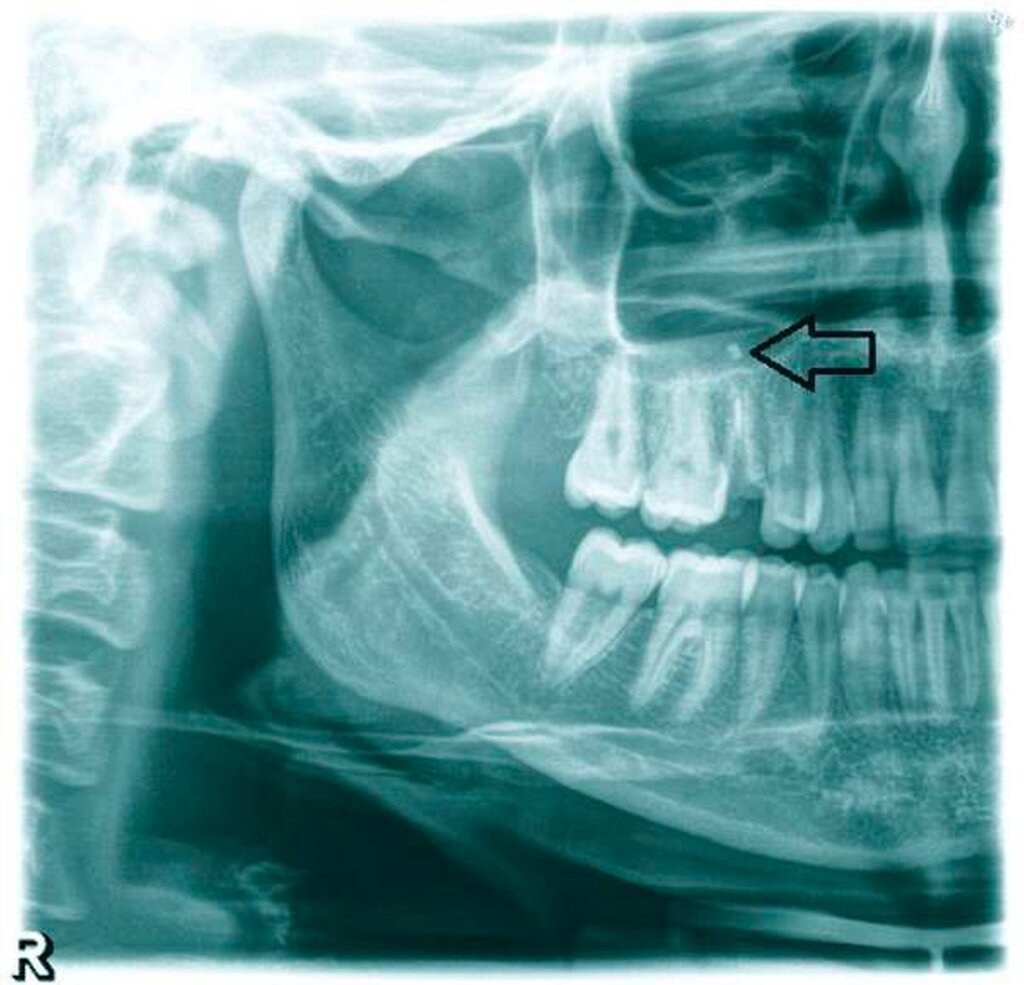

Eine Wiedervorstellung erfolgte erst sieben Monate später, nun aber als „Schmerzpatientin“. Der Zahn 15 war perkussionsempfindlich und die Patientin beklagte ein zunehmendes Druckgefühl über der Kieferhöhle rechts, das durch Klopfen in der Region zu provozieren war. In der präoperativen Panoramaschichtaufnahme war der apikale Fremdkörper deutlich erkennbar (Abbildung 1). In Analgosedierung erfolgte die operative Entfernung des nicht erhaltungswürdigen Zahns. Da die Entfernung des Fremdkörpers über die Extraktionsalveole nicht gelang, wurde ein Zugang über der fazialen Kieferhöhlenwand angelegt.